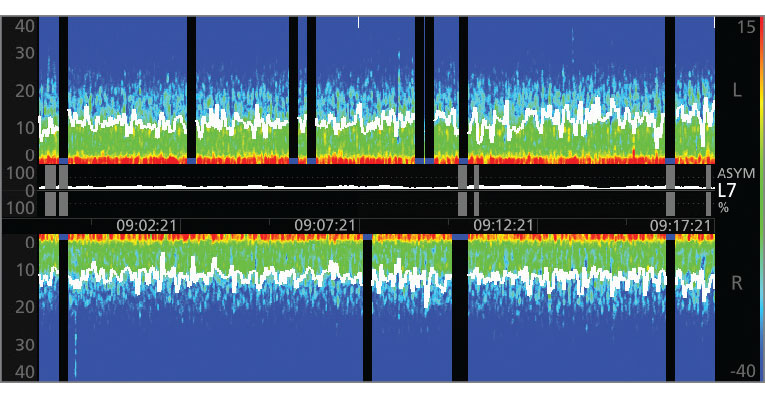

The Power of the Density Spectral Array (DSA)

SedLine offers the flexibility of choosing to display either an enhanced Multitaper Density Spectral Array (DSA) or a standard Hanning DSA.

Understand the DSA

The DSA represents the power of the EEG on both sides of the brain, alongside other patient information provided by SedLine sensors. Watch the video to learn more.